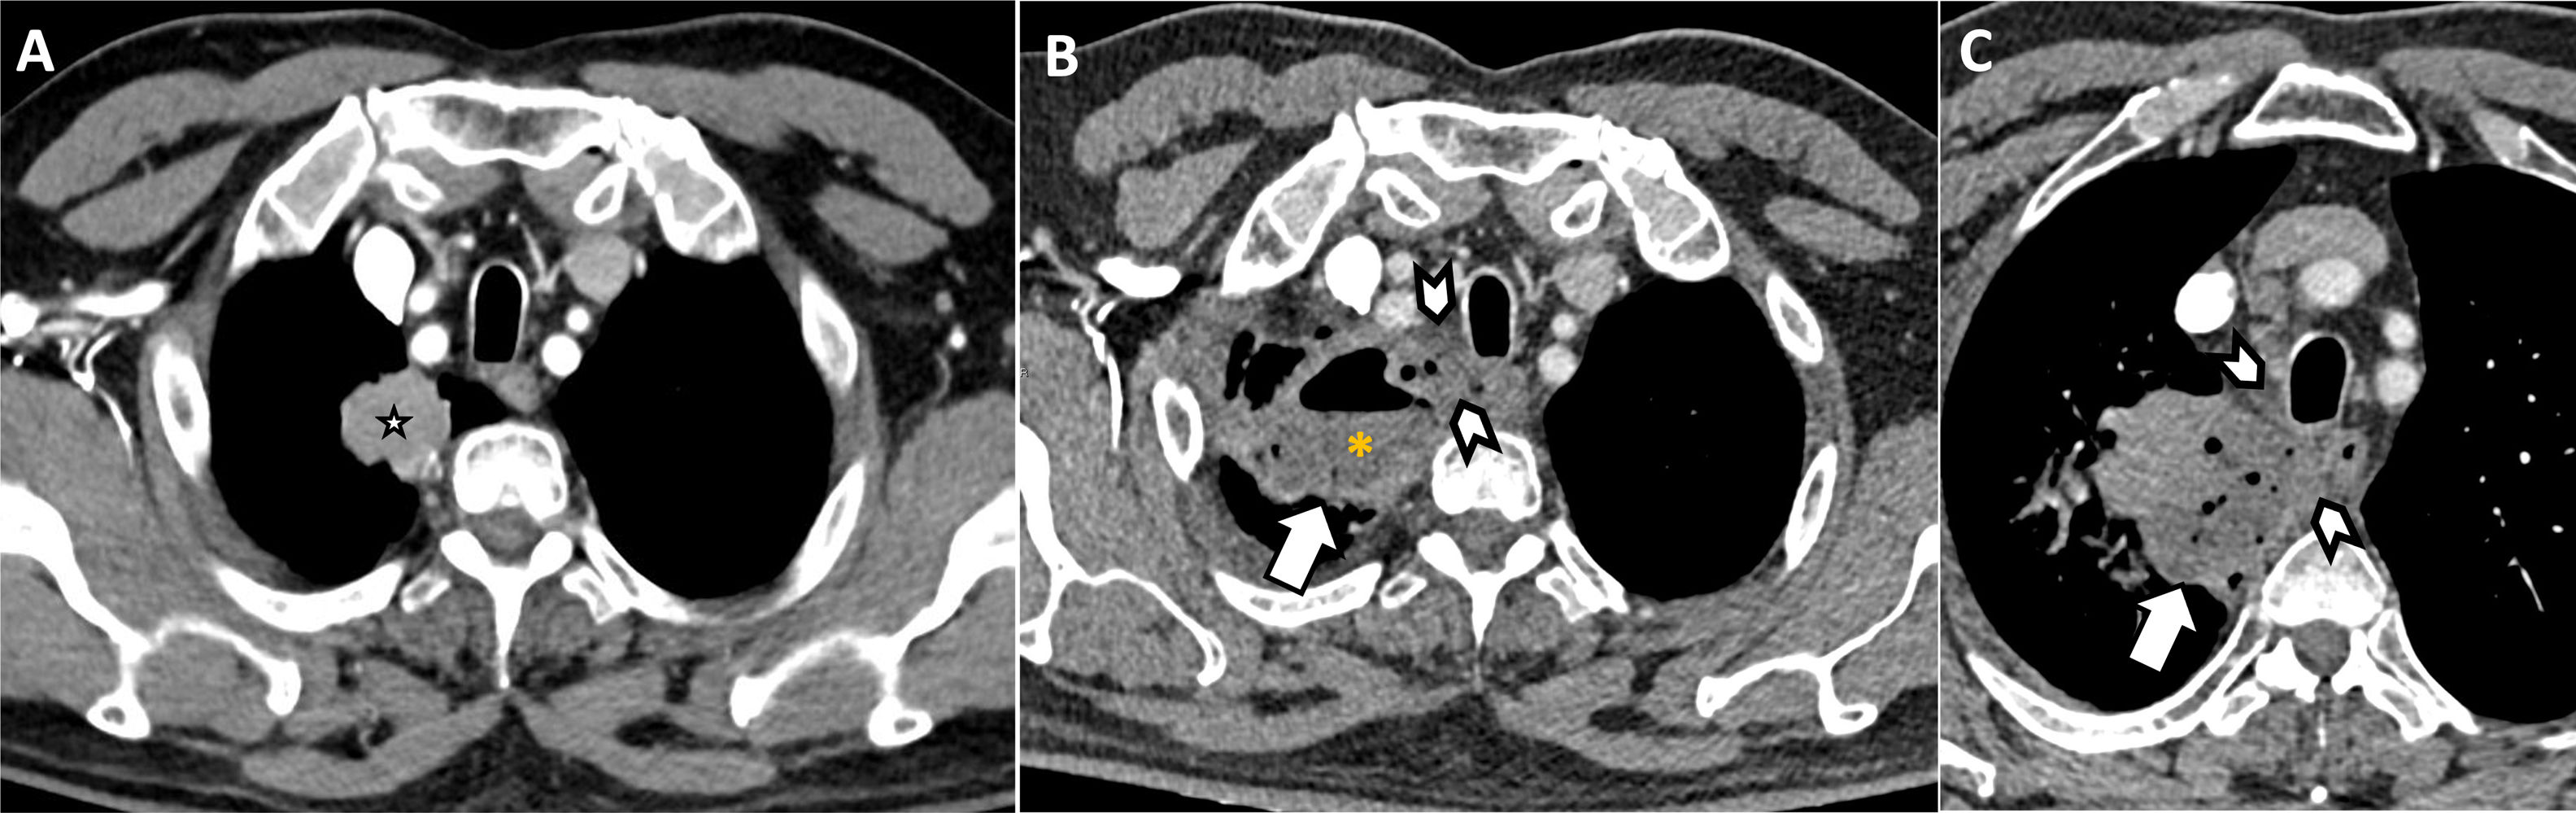

Urgencias asociadas a procedimientos diagnósticosLos procedimientos diagnósticos (biopsias percutáneas, ecoendoscopia con punción), aunque muchos de ellos mínimamente invasivos y seguros, pueden asociar complicaciones (hemorragias, infecciones, pseudoaneurismas…). La punción-aspiración transbronquial guiada por ecografía endobronquial (EBUS-TBNA) presenta una tasa de complicaciones inferior al 1,5%, siendo el sangrado una de las más comunes17,18. Entre las complicaciones graves, aunque raras, destacan la mediastinitis/absceso mediastínico, la formación de fístulas o de pseudoaneurismas bronquiales o pulmonares. La TC torácica permite detectar alteración de la atenuación grasa mediastínica post-punción, que, junto a otros hallazgos, puede sugerir la presencia de mediastinitis (fig. 7). Por su parte, la angio-TC permite el diagnóstico de los pseudoaneurismas que típicamente presentan la misma densidad que el vaso del que dependen en todas las fases del estudio19. Debido a su elevado riesgo de rotura, su tratamiento, generalmente intravascular mediante coils o plugs, está indicado independientemente de su tamaño o localización (fig. 8).

Varón de 59 años que acude a urgencias por dolor torácico centrotorácico punzante. Se sometió a una biopsia de una adenopatía subcarinal hace 7días para valorar posible afectación metastásica. Angio-TC torácica sin (A) y tras la administración intravenosa de contraste (B-C) que muestra un hematoma mediastínico (asterisco) cuyos valores de atenuación no se modifican en las distintas fases del estudio. En la fase arterial (B) se identifica una pequeña imagen pseudonodular (punta de flecha) dependiente de la arteria bronquial derecha, localizada en la región subcarinal adyacente a la adenopatía puncionada. La formación vascular no se logra identificar en la fase venosa (C), descartando que corresponda con un punto de sangrado activo. D)Reconstrucción de máxima intensidad (MIP) en plano coronal modificado que confirma la presencia de un pseudoaneurisma dependiente de la arteria bronquial (punta de flecha). E)Arteriografía supraselectiva de la arteria bronquial derecha que confirma la presencia de un pseudoaneurisma (punta de flecha), con morfología esférica y un diámetro aproximado de 10mm, situado en una bifurcación de la arteria bronquial inferior derecha.